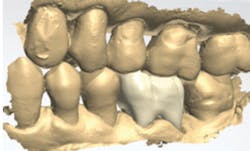

Figures 2 and 3: Additional restorations using Lava Esthetic